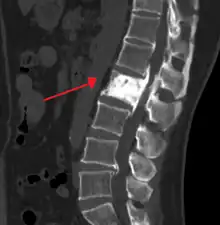

The exact cause is unknown, although leading theories indicate both genetic and acquired factors (see Causes). Paget's disease may affect any one or several bones of the body (most commonly pelvis, tibia, femur, lumbar vertebrae, and skull), but never the entire skeleton,[1][2][3] and does not spread from bone to bone.[4] Rarely, a bone affected by Paget's disease can transform into a malignant bone cancer.

- Pagetic bone has a characteristic appearance on X-rays. A skeletal survey is therefore indicated.

- Bone scans are useful in determining the extent and activity of the condition. If a bone scan suggests Paget's disease, the affected bone(s) should be X-rayed to confirm the diagnosis.

The disease is progressive and slowly worsens with time, although people may remain minimally symptomatic. Treatment is aimed at controlling symptoms, but there is no cure. Any bone or bones can be affected, but Paget's disease occurs most frequently in the spine, skull, pelvis, femur, and lower legs. Osteogenic sarcoma, a form of bone cancer, is a rare complication of Paget's disease occurring in less than one percent of those affected. The development of osteosarcoma may be suggested by the sudden onset or worsening pain.